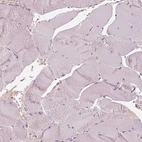

Immunohistochemical staining of human eye, retina shows moderate positivity in photoreceptor cells and nerve fibers.